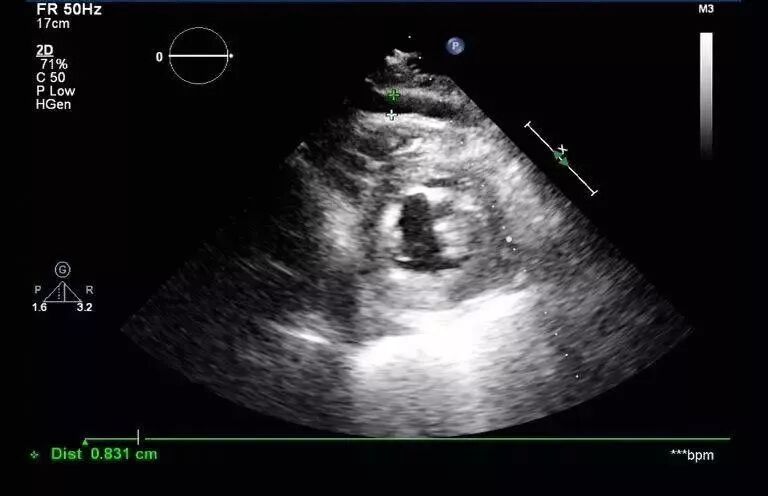

图1和图2 :术中行心包积液彩超可见:心包腔内见液性暗区:右房顶部  20mm,右室前壁最多时25 mm,右室侧壁旁15 mm。提示:心包积液(中大量)。

视频1:左室心尖可见团块状低回声,疑似血肿。

为进一步明确诊断,行床旁心脏超声造影,可见Contrast-LVO模式下,可见心包腔内可见由左室心尖缓慢飘出的点状造影剂声像。